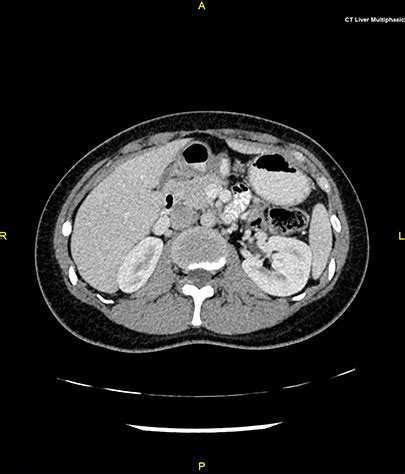

This is a ct scan of any one body part:

I was involved in a road accident and had no idea what was wrong with me; Without this scan, my provider would not have been able to get a clear picture of the small bones in my neck and how they may be affecting my back. If your doctor recommends a ct scan, ask about the potential benefits to your health, which generally greatly outweigh any small potential risk from radiation. Are there open ct scanners? What's the doctor going to say? 300 reviews from people who purchased this procedure. Get the best price for a ct scan without ct scan without contrast. This is a ct scan of any one body part: Having a ct scan can be an unnerving experience. Ct stands for computerised tomography. This provides a series of images from many different angles. We recommend preparing a list of questions to ask the to get a more accurate cost, you can get a personalised quote from private healthcare uk. Both mri scans and ct scans can be used to determine the best biopsy site to get a definitive diagnosis of cancer.